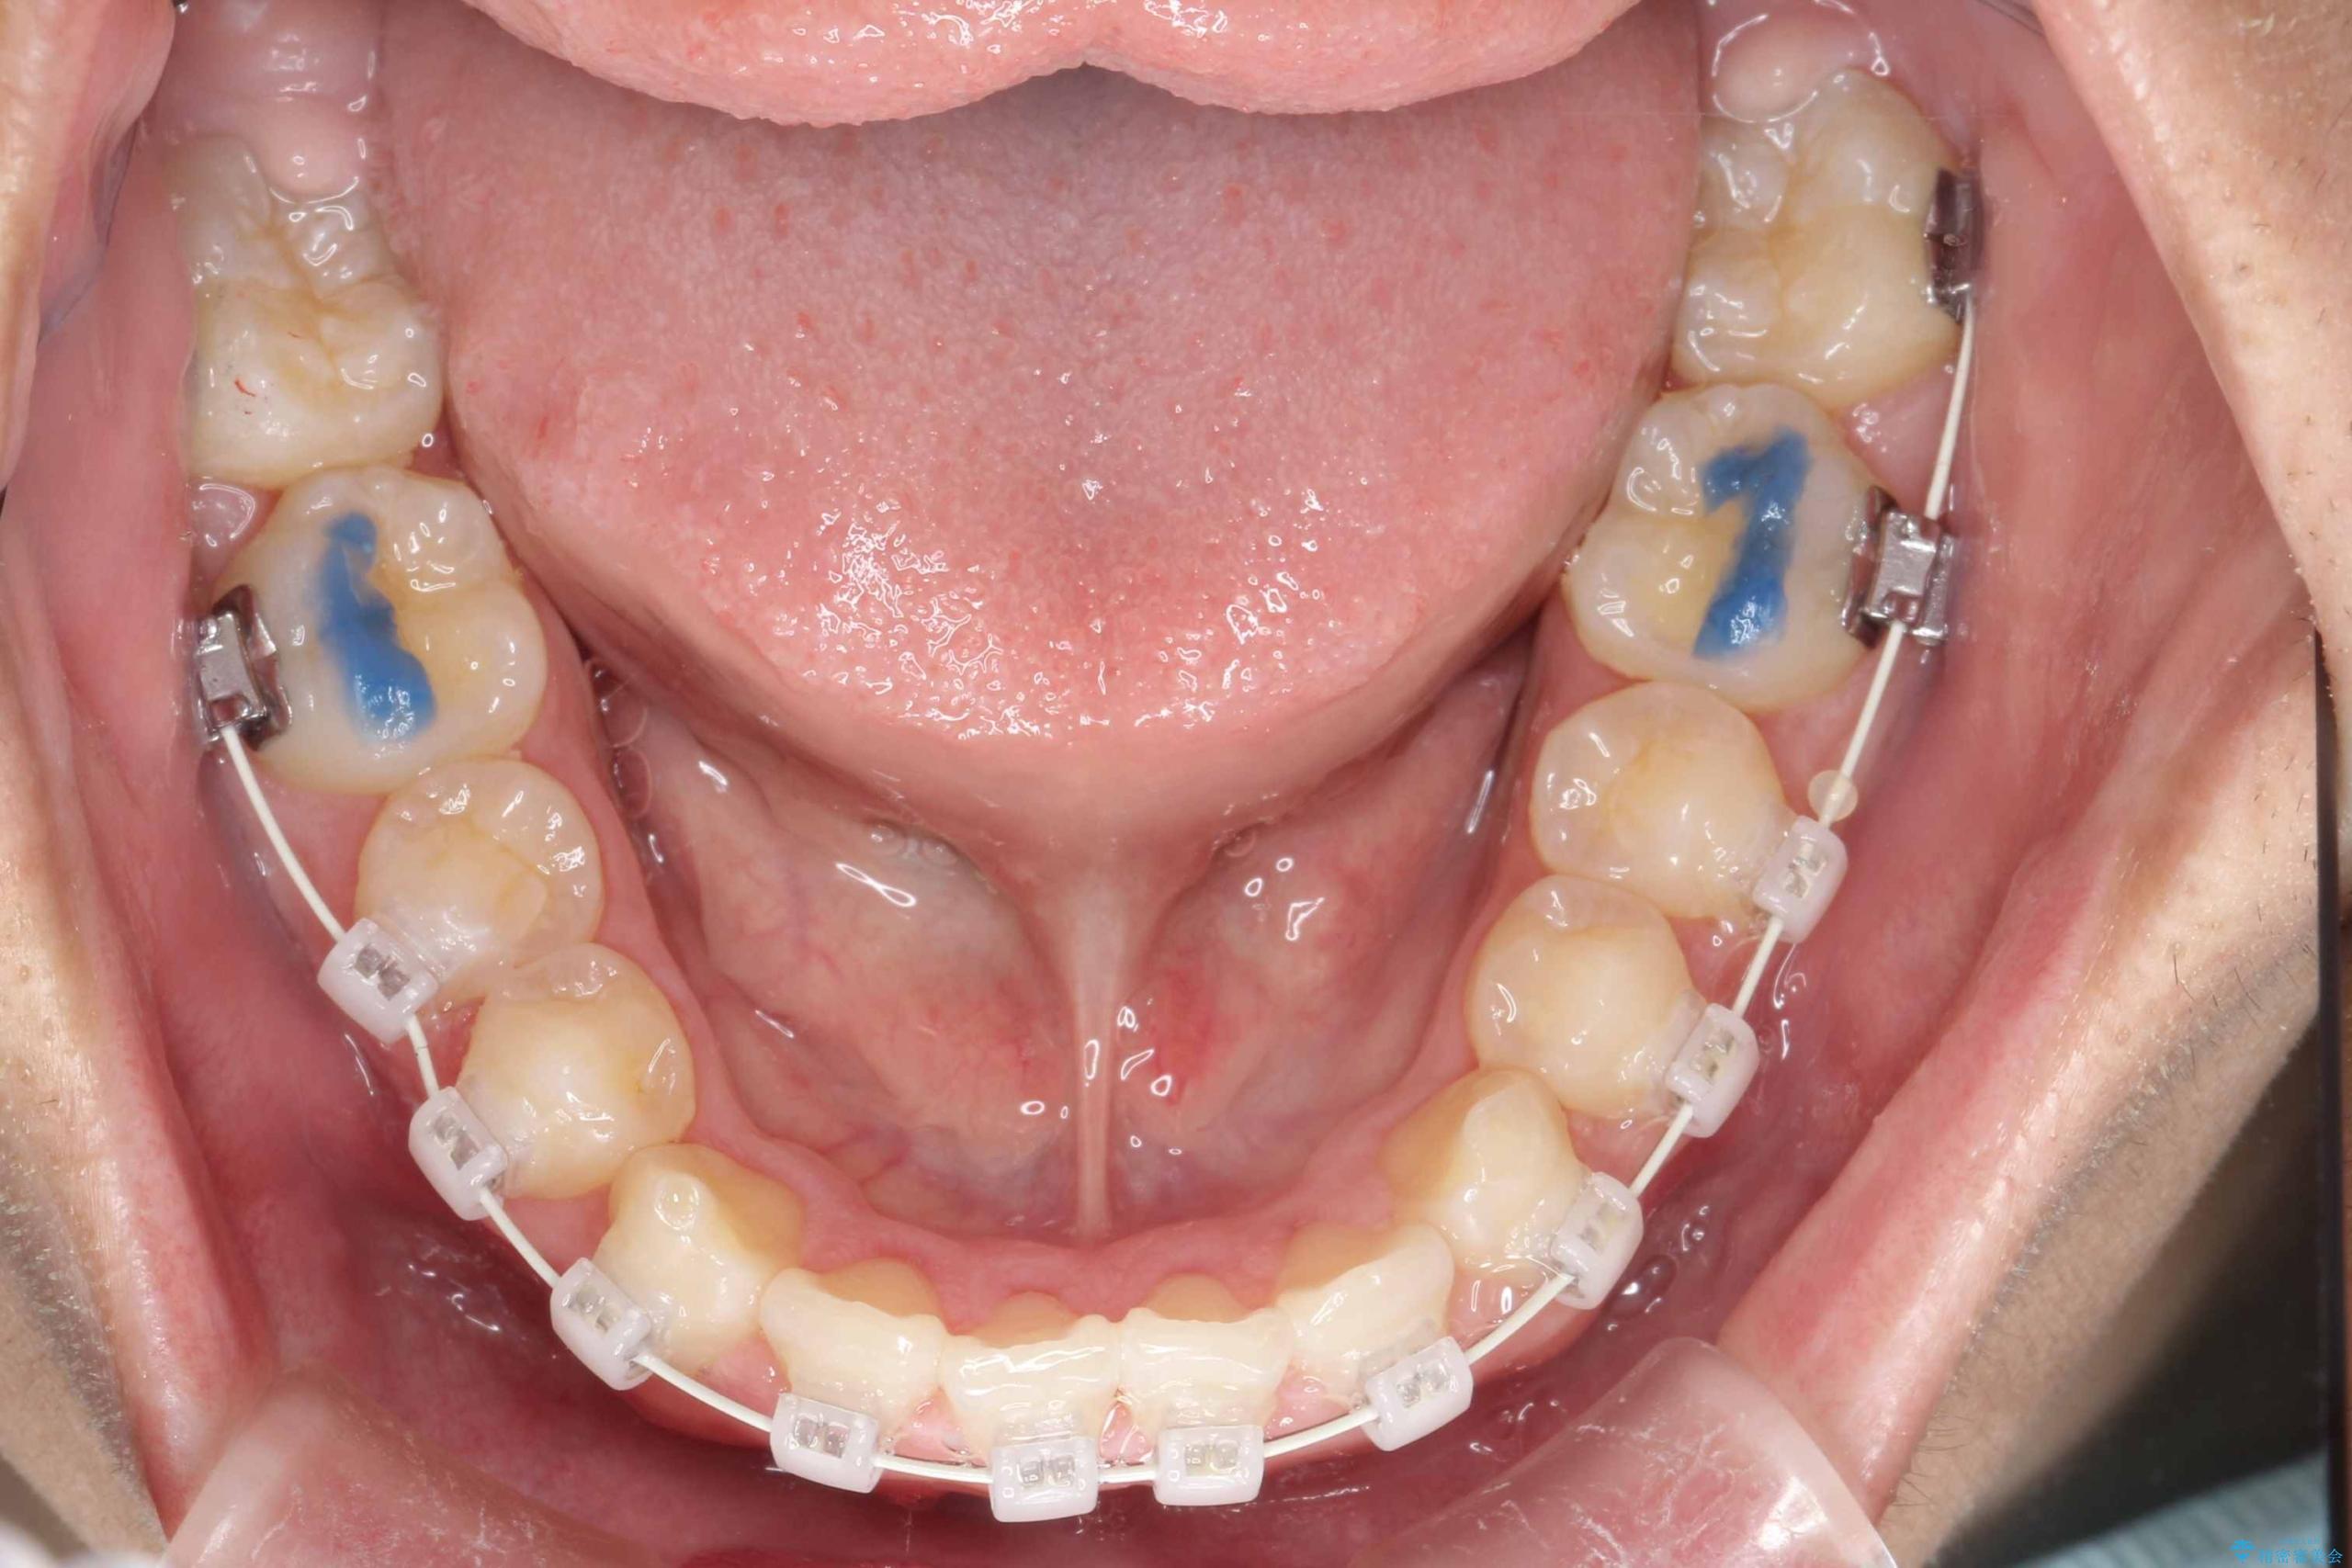

八重歯・歯並びのデコボコとディープバイトを改善した抜歯ワイヤー矯正症例

- ワイヤー(審美装置)

矯正の精密検査の結果上顎左右4番の計2本を抜歯し、審美性に配慮したワイヤー矯正装置(審美装置)を用いて治療を行いました。

八重歯などの歯列のデコボコが綺麗に改善され、患者様にも大変喜んでいただけました。また、咬み合わせが深い「ディープバイト」も併せて改善し、見た目だけでなく機能面でもバランスの取れた咬合を獲得しています。